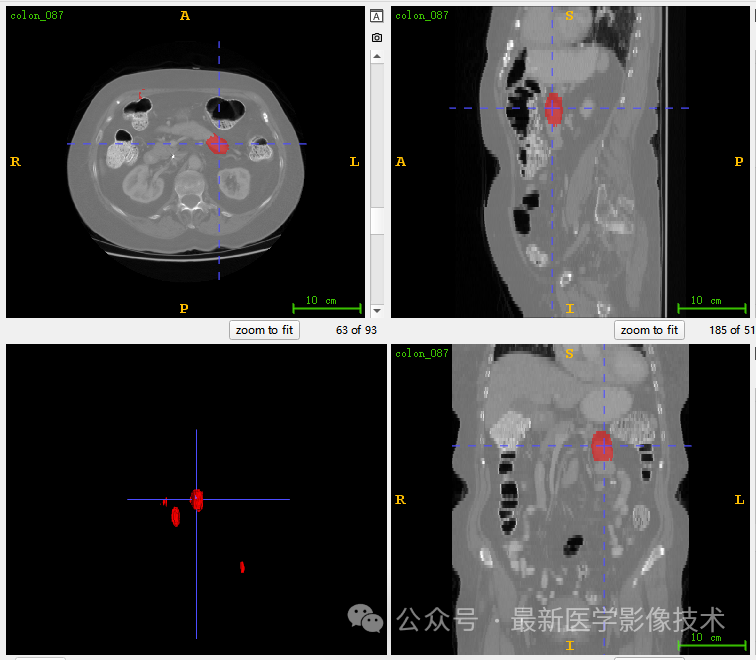

5、验证集分割结果

左图是金标准结果,右图是预测结果。